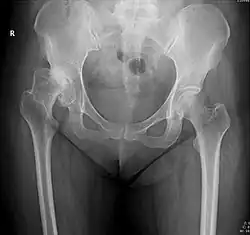

X-ray of the hips of a 40-year-old female, with dysplasia of her right hip.

In the adult hip there are important landmarks to be recognized on plain film radiographs:[3]